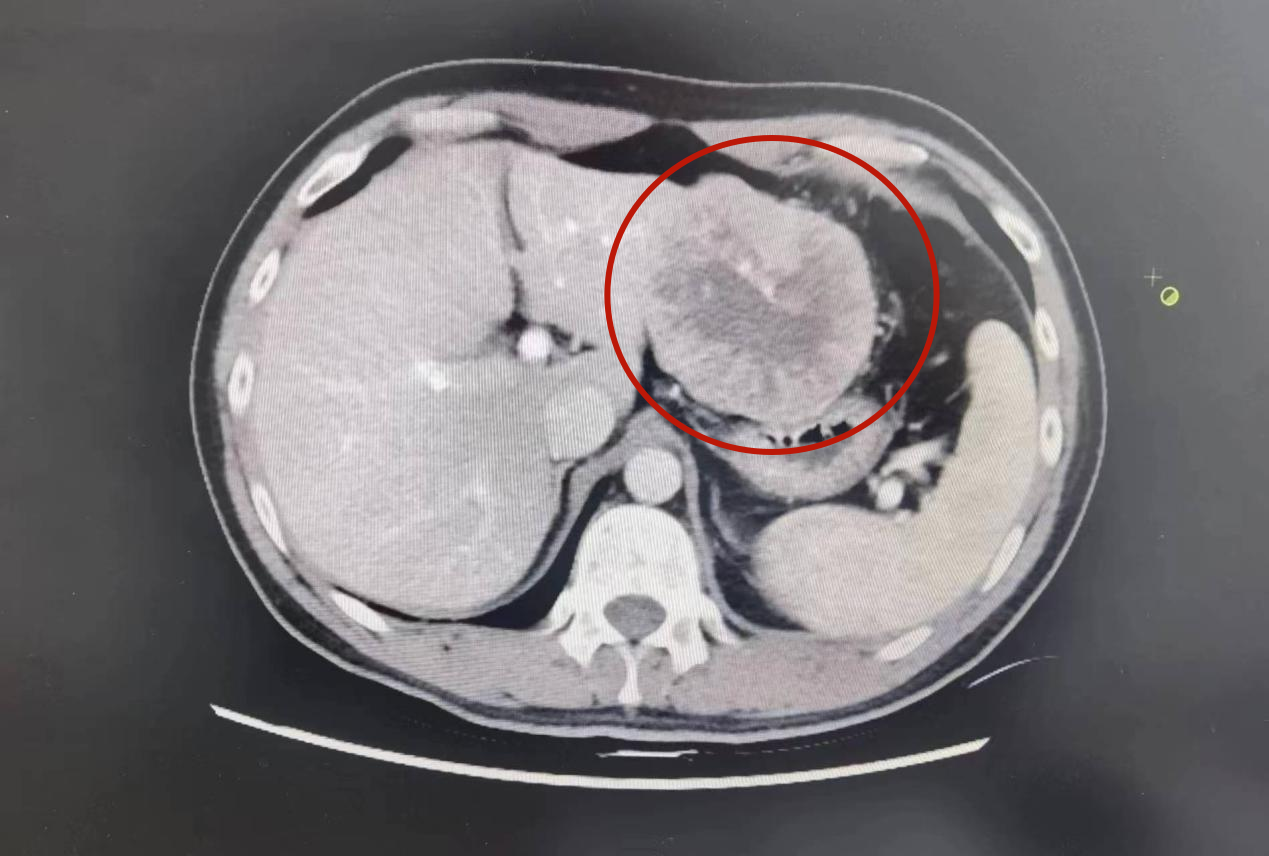

近日,我院普外科成功为一名33岁的肝癌患者实施腹腔镜下肝癌根治术,精准切除患者病灶肿瘤。该手术的成功开展,不仅让患者在家门口享受到了高水平的医疗服务,也标志着我院腹腔镜微创技术日益成熟。

在征得患者及家属同意并完善相关术前准备后,普外科团队为王先生行“腹腔镜下肝癌切除术”。术中探查见:肝轻度硬化,左肝II、III段外缘可及外生型肿瘤,局部大网膜包裹粘连,胃、膈肌未及侵犯。手术过程中生命体征保持平稳,医生团队专业、细致地进行手术操作,手术顺利完成。